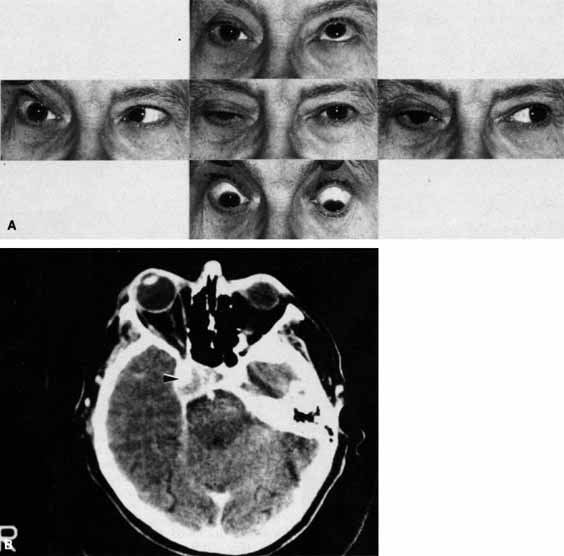

A 70-year-old woman presented with a 6-month history of progressive diplopia and ptosis. She demonstrated complete right third, fourth, and sixth cranial nerve palsies, and hypesthesia of cranial nerve V1 (Fig. 22A). The right pupil was dilated. Computed tomography (CT) disclosed an intracavernous aneurysm (see Fig. 22B).

Fig. 22 A. A 70-year-old woman with complete right third, fourth, and sixth cranial nerve palsies. Hypesthesia of cranial nerve V1 was also present. B. CT scan demonstrates an intracavernous aneurysm (arrow).

The so-called superior orbital fissure syndrome occurs when an infiltrative, inflammatory, or ischemic event occurs within the superior orbital fissure, but not in the orbital apex.4 A complete superior orbital fissure syndrome occurs when all the neurovascular components passing through the superior orbital fissure are damaged, producing a total ophthalmoplegia, ptosis, and anesthesia of cranial nerve V1 (see Fig. 22A). The pupil may be dilated, miotic, or midposition and fixed, depending on the balance of parasympathetic and sympathetic damage. The superior ophthalmic vein, best seen on CT, may be dilated if venous outflow from the orbit is obstructed. Clues to venous outflow obstruction are increased intraocular pressure, fullness of the upper eyelid, and hyperemia of the deep Tenon's vessels. Ophthalmoscopically, the retinal veins may be dilated. The effect of a lesion in the superior orbital fissure or the anterior cavernous sinus cannot be differentiated clinically (see Fig. 22B). When the posterior cavernous sinus becomes involved, hypesthesia of cranial nerve V2 may also be present.

The only difference between a superior orbital fissure syndrome and an orbital apex syndrome is the presence of visual loss caused by optic nerve involvement. Visual acuity, color vision, or the visual field are abnormal. An ipsilateral relative afferent pupil defect is present.